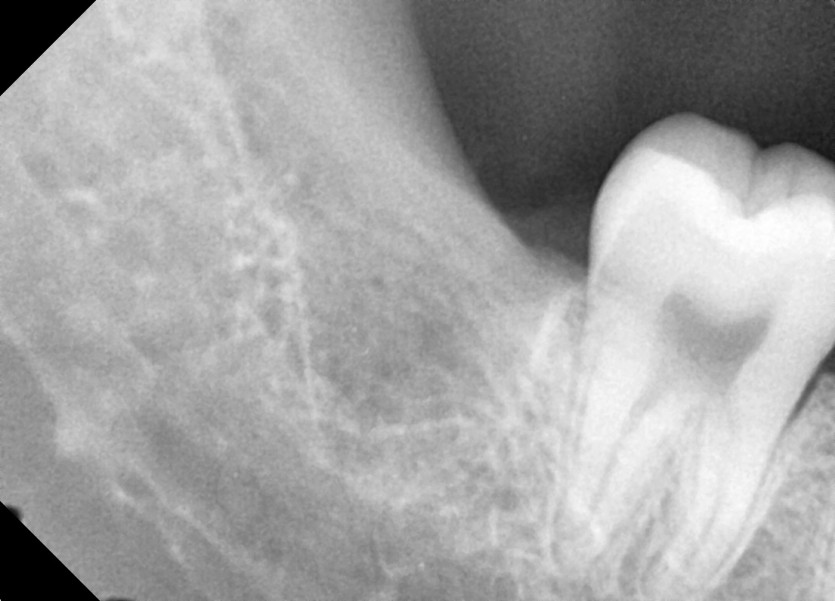

#18,28,38,48 사랑니 발치

구강 외과 전문의가 당일 발치했습니다.